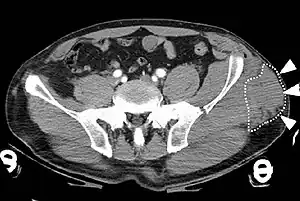

| A Morel-Lavallée lesion is a closed traumatic soft-tissue degloving injury, caused by separation of the hypodermis from the underlying fascia.[1] It most frequently occurs in the peritrochanteric region along the proximal lateral thigh,[1] such as in this CT scan. |